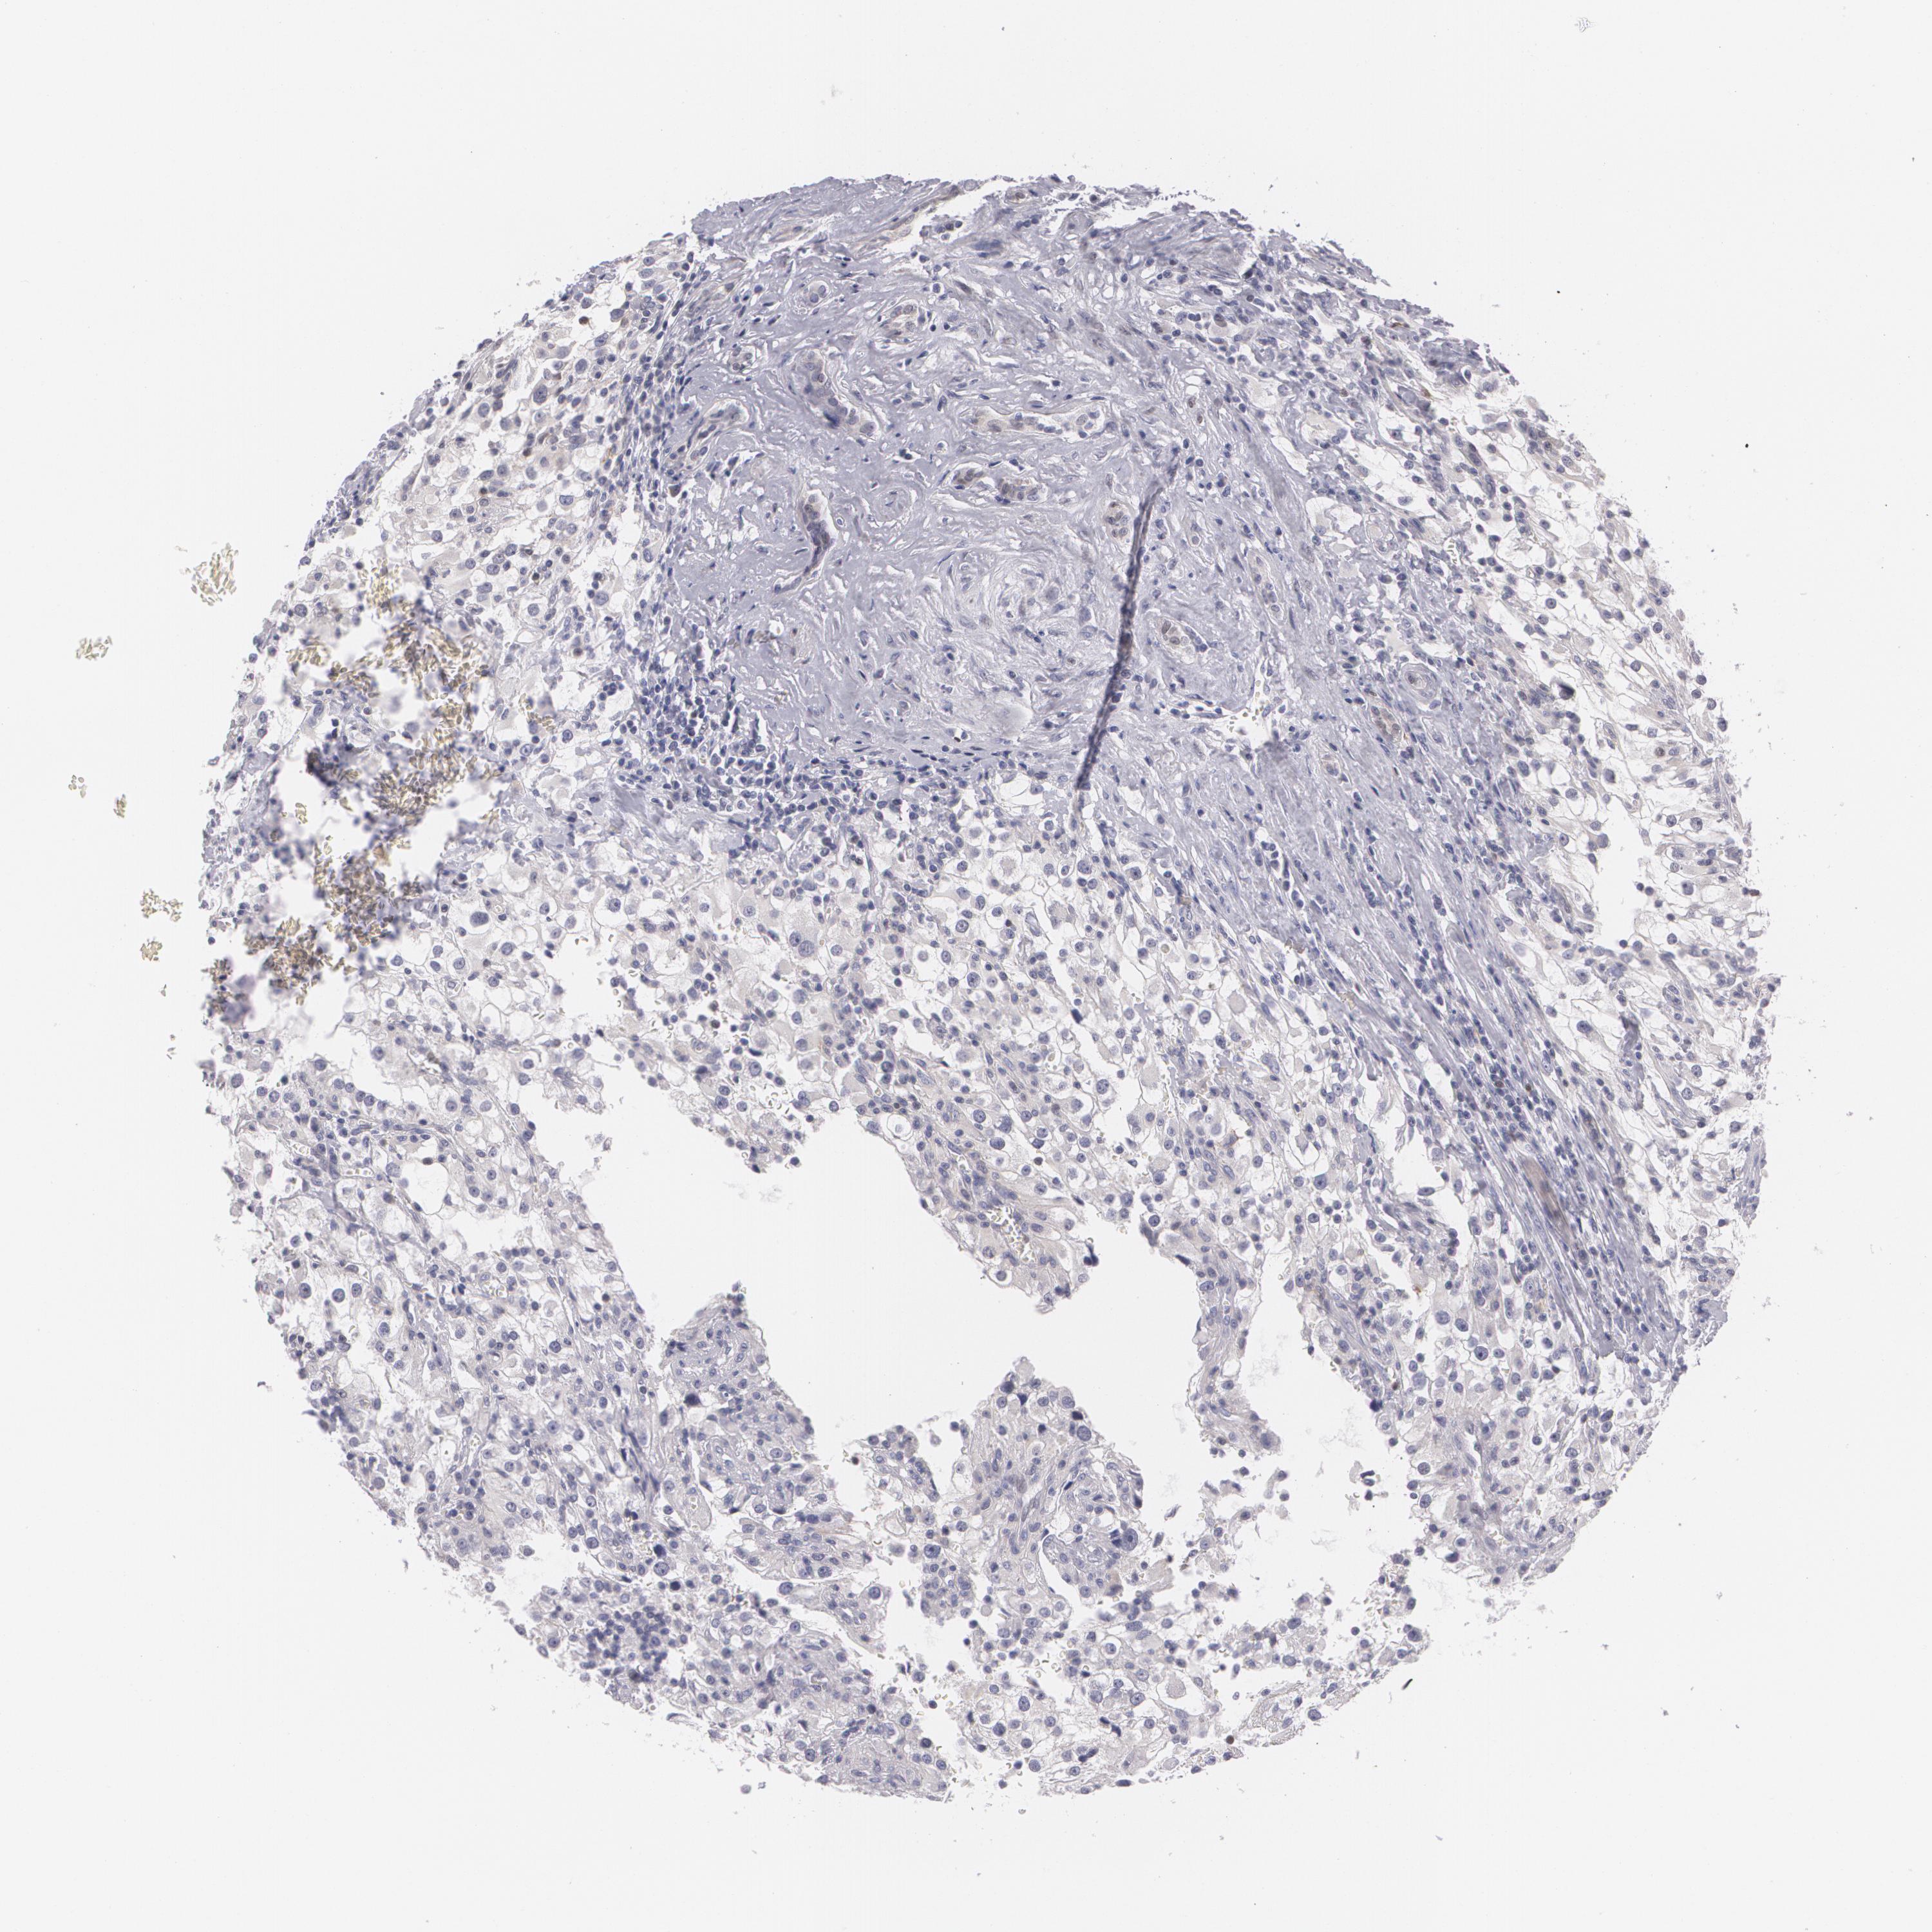

KIDNEY RENAL CLEAR CELL CARCINOMA (VALIDATION) - Interactive survival scatter ploti

The Survival Scatter plot shows the clinical status (i.e. dead or alive) for all individuals in the patient cohort, based on the same data that underlies the corresponding Kaplan-Meier plots. Patients that are alive at last time for follow-up are shown in blue and patients who have died during the study are shown in red.

The x-axis shows the expression levels (FPKM) of the investigated gene in the tumor tissue at the time of diagnosis. The y-axis shows the follow-up time after diagnosis (years). Both axes are complimented with kernel density curves demonstrating the data density over the axes. The top density plot shows the expression levels (FPKM) distribution among dead (red) and alive patients (blue). The right density plot shows the data density of the survived years of dead patients with high and low expression levels respectively, stratified using the cutoff indicated by the vertical dashed line through the Survival Scatter plot. This cutoff is automatically defined based on the FPKM cutoff that minimizes the p-score. The cutoff can be changed by dragging the vertical line or by entering a cutoff value in the square labeled "Current cut-off".

Under the Survival Scatter plot the p-score landscape (black curve; left axis) is shown together with dead median separation (red curve; right axis). Dead median separation is the difference in median mRNA expression between patients who have died with high and low expression, respectively. It is calculated as follows: median FPKM expression of dead patients with high expression - median FPKM expression of dead patients with low expression. This is intended to aid the user in visually exploring custom cutoffs and the associated p-scores and dead median separation.

Individual patient data is displayed and can be filtered by clicking on one or more of the category buttons on the top of the page. Categories describing expression level and patient information include: high, low, alive, dead, female, male and tumor stages. The scale of the x-axis can be toggled between linear and log-scale by clicking on the "x log" button. Mouse-over function shows TCGA ID, patient information and mRNA expression (FPKM) for each patient.

& Survival analysisi

Kaplan-Meier plots summarize results from analysis of correlation between mRNA expression level and patient survival. Patients were divided based on level of expression into one of the two groups "low" (under cut off) or "high" (over cut off). X-axis shows time for survival (years) and y-axis shows the probability of survival, where 1.0 corresponds to 100 percent.

ZBTB16 is not prognostic in Kidney Renal Clear Cell Carcinoma (validation)

Best expression cut offi

Based on the FPKM value of each gene, patients were classified into two groups and association between prognosis (survival) and gene expression (FPKM) was examined. The best expression cut-off refers the FPKM value that yields maximal difference with regard to survival between the two groups at the lowest log-rank P-value. Best expression cut-off was selected based on survival analysis .

When clicking on this number, the vertical dashed line indicating cut-off, the interactive survival plot, and the Kaplan-Meier curve will be adjusted to show results based on the best expression cut-off.

: 9.86

P scorei

Log-rank P value for Kaplan-Meier plot showing results from analysis of correlation between mRNA expression level and patient survival.

N/A

TCGA RNA samplesi

RNA-seq data is reported as average FPKM (number Fragments Per Kilobase of exon per Million reads), generated by the The Cancer Genome Atlas (TCGA) .

Normal distribution across the dataset is visualized with box plots, shown as median and 25th and 75th percentiles. Points are displayed as outliers if they are above or below 1.5 times the interquartile range. FPKM values of the individual samples are presented next to the box plot.

Average pTPM 15.2

Number of samples 100